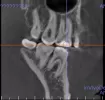

На снимке видно потемнение под пломбой, из-за этого может болеть зуб?

У меня периодически болит зуб, то ли 6-ка, то ли 7-ка.Тточно не могу определить какой зуб болит.

Сходил в местную стоматологию. Там сказали, что все нормально. Сделали КЛКТ. Боль ноющая, может болеть день, потом сама по себе утихает. Иногда очень сильно болит, голова начинает от этого болеть. И так раз в неделю, две, три.

Начал сам более детально снимок рассматривать, показалось, что потемнение под пломбой. Реакции, когда пью холодное или горячее никакой нет.

Так и должно быть? Надо идти повторно и просить, чтобы вскрывали зуб?

Ваш снимок должен смотреть специалист в разных ракурсах, так сложно сказать. Вам необходимо обратиться к стороннему специалисту со снимком для консультации.